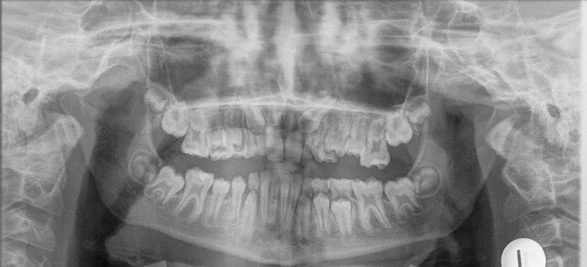

This OPG shows that the second molars are slightly past the point of ideal development